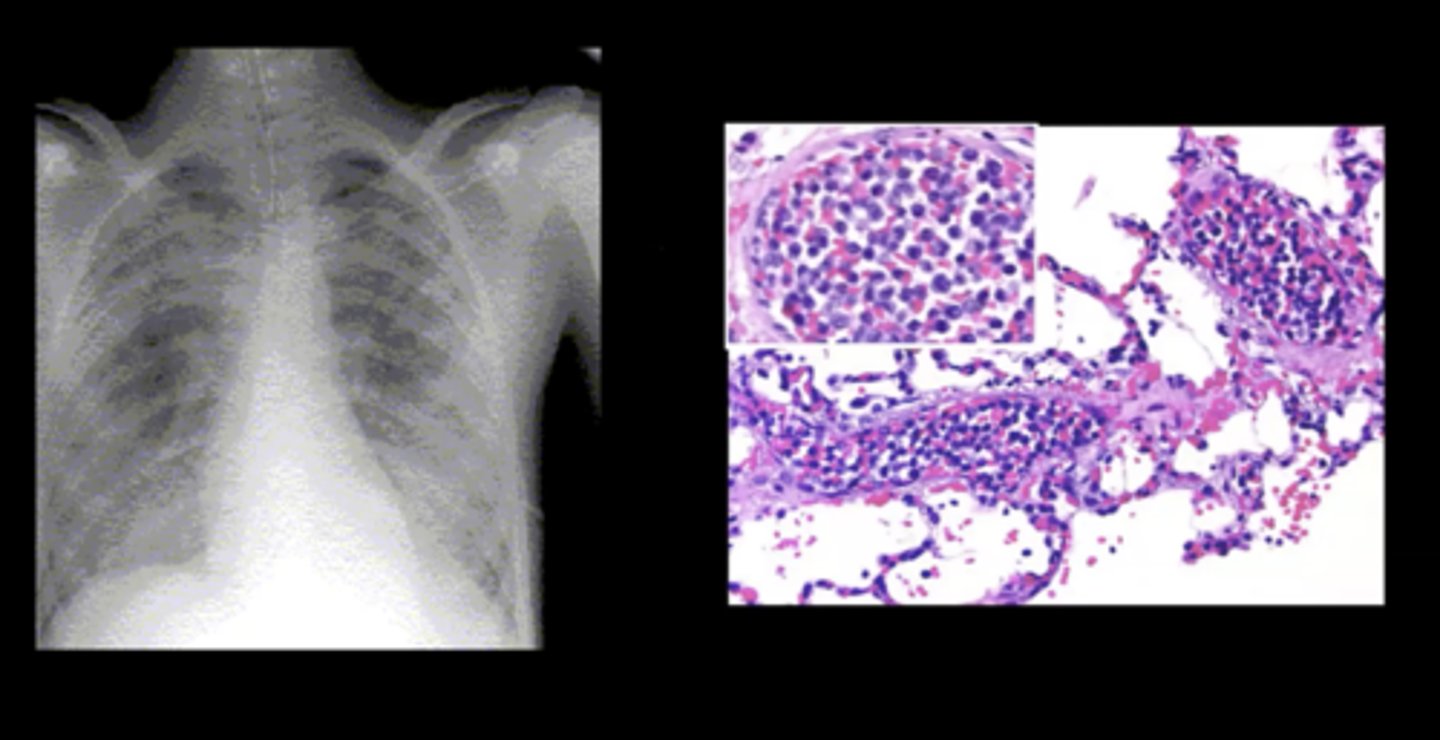

Pulmonary leukostasis

Sudden shortness of breath and progressive dyspnea; caused by a WBC clot

Hodgkin's lymphoma (HL)

Definition: Tumor that originates in ONE single lymph nodes --> spread to other nodes

Pathogenesis: B cells transform into large, abnormal cells (Reed-Sternberg cells)

S+S: Painless enlargement of lymph nodes above the diaphragm, fever, weight loss

Treatment: Chemo and radiation